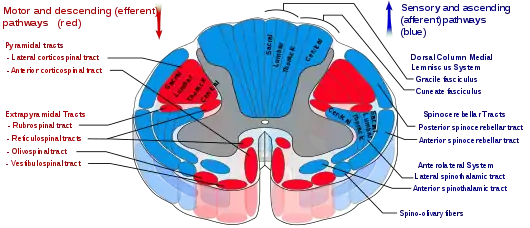

Spinal cord tracts, with pyramidal tracts labeled at upper left | |

Corticospinal tract

Nerve fibres in the corticospinal tract originate from pyramidal cells in layer V of the cerebral cortex. Fibres arise from the primary motor cortex (about 30%), supplementary motor area and the premotor cortex (together also about 30%), and the somatosensory cortex, parietal lobe, and cingulate gyrus supplies the rest.[2] The cells have their bodies in the cerebral cortex, and the axons form the bulk of the pyramidal tracts.[4] The nerve axons travel from the cortex through the posterior limb of internal capsule, through the cerebral peduncle and into the brainstem and anterior medulla oblongata. Here they form two prominences called the medulla oblongatary pyramids. Below the prominences, the majority of axons cross over to the opposite side from which they originated, known as decussation. The axons that cross over move to the outer part of the medulla oblongata and form the lateral corticospinal tract, whereas the fibres that remain form the anterior corticospinal tract.[2] About 80% of axons cross over and form the lateral corticospinal tract; 10% do not cross over and join the tract, and 10% of fibres travel in the anterior corticospinal tract.

The nerve axons traveling down the tract are the efferent nerve fibers of the upper motor neurons. These axons travel down the tracts in the white matter of the spinal cord until they reach the vertebral level of the muscle that they will innervate.[5] At this point, the axons synapse with lower motor neurons. The majority of axons do not directly synapse with lower motor neurons, but instead synapse with an interneuron that then synapses with a lower motor neuron. This generally occurs in the anterior grey column.[2] Nerve axons of the lateral corticospinal tract that did not cross over in the medulla oblongata do so at the level of the spinal cord they terminate in.[6]

The extrapyramidal system refers to tracts within the spinal cord involved in involuntary movement but not part of the pyramidal tracts.[2] Their functions include the control of posture and muscle tone.

Diagram of the principal fasciculi of the spinal cord, from Gray's anatomy

Diagram of the principal fasciculi of the spinal cord, from Gray's anatomy